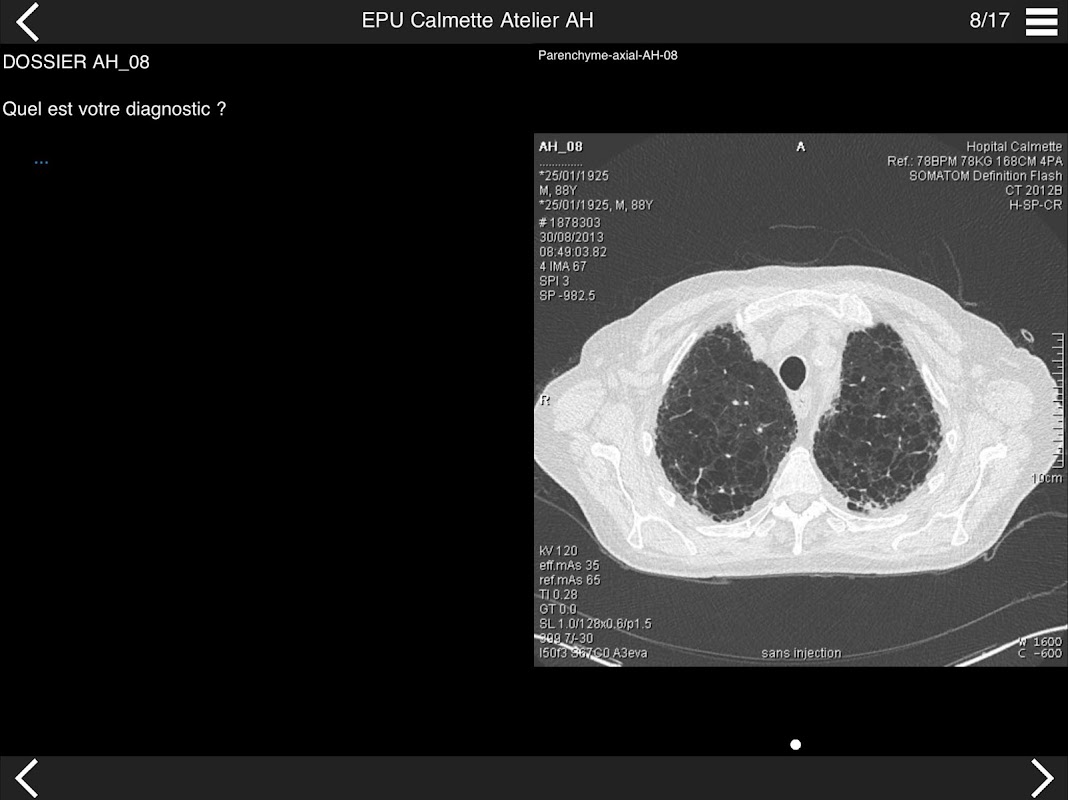

Retrouvez les cas cliniques du Cours intensif de TDM multicoupe du thorax dans cette application.

Thèmes du cours 2017 :

* Pathologie interstitielle : lésions élémentaires et « patterns »